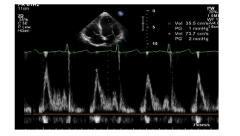

5.4. Siêu âm Doppler mô cơ tim

- Kiểm tra chế độ TDI của máy.

- Thực hiện trên mặt cắt 4 buồng tim từ mỏm.

- Điều chỉnh cursor sao cho chùm tia trùng với thành tim ( < 20 độ)

- Đặt cửa sổ Doppler đúng vị trí vòng van hai lá, kích thước 3 mm nếu ghi ở vách liên thất, 5 mm nếu ghi ở thành bên.

- Bật chế độ TDI.

- Giảm gain xuống < 25 cm/s

- Điều chỉnh tốc độ quét của chùm tia siêu âm (sweep speed):50 - 100 m/s.

- Hướng dẫn cho người bệnh thở ra, hít vào, ghi TDI cuối kỳ thở ra, khi người bệnh nín thở.

Hình 12. Hình ảnh siêu âm Doppler mô cơ tim tại vòng van hai lá.